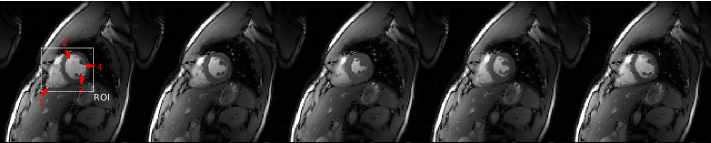

For both of the datasets, the fully sampled data is retrospectively by discarding a random subset of the samples along the vertical axis in each temporal frame, with varying subsampling patterns in different frames. The distribution of the selected samples is uniform along the temporal axis for any given vertical position and Gaussian along the vertical axis centered on zero frequency coefficients in spatial Fourier transform domain. Experiments are performed at subsampling rates R=8,10,12,and 14 (R=8 denotes 1/8181/8 of all the samples). The datasets are normalized so that the reconstruction of the fully sampled data leads to images with maximum intensity of 1. Sample frames from fully sampled reconstructions of the datasets can be seen in Figure 2.

The datasets had no global motion but only local motion which was especially significant around the heart area, therefore the region around the heart shown in Figure 2 is considered as the region of interest (ROI) when evaluating the reconstruction quality. Diffeo-symmetric Demon’s registration algorithm with the recommended parameters in [28] is used as the deformable registration algorithm in order to estimate the motion in line 4 of Algorithm 2 as well as line 21 of Algorithm 3. The algorithm is applied without any multi-resolution scheme and is slightly modified to be applicable to complex valued datasets. The initial reconstruction step is accomplished with TV regularization for Motion-TV while ΦtsubscriptΦ𝑡\Phi_{t} is selected as temporal DFT for Joint Motion-TV. Bilinear interpolation is used for motion compensation in formulating 𝐊𝐭(𝐯)subscript𝐊𝐭𝐯{\mathbf{K}_{\mathbf{t}}({\mathbf{v}})}.

The root mean squared error (RMSE) in the ROI of each frame with respect to fully sampled reconstructions are plotted in Figure 3 while the overall RMSE is listed in Tables LABEL:tab:RMSE1 and LABEL:tab:RMSE2. It can be seen that the RMSE improvement with respect to TV reconstruction is small in Dataset 1 but is quite significant in Dataset 2. This can be explained by the fact that the magnitude of motion vectors are much smaller in Dataset 1 and mostly not even greater than a single pixel (can be seen in Figure 6). Therefore the benefit of Motion-TV is limited. As the resolution and the scale of motion increase, the benefit of Motion-TV and Joint Motion-TV over TV and DFT can be seen more clearly in terms of RMSE in Figure LABEL:fig:RMSE2 and Table LABEL:tab:RMSE2. The lower sparsity of temporal TV and DFT manifest as spatial noise or temporal blurring which can be observed in the samples shown in Figure 4.

Figure 4: Reconstructed samples from all datasets (frame 4). In all figures, from left to right, fully sampled, DFT, TV, Motion-TV and Joint Motion-TV reconstruction is shown. First row is the reconstruction at subsampling rate R=8 and the second row is at rate R=14.